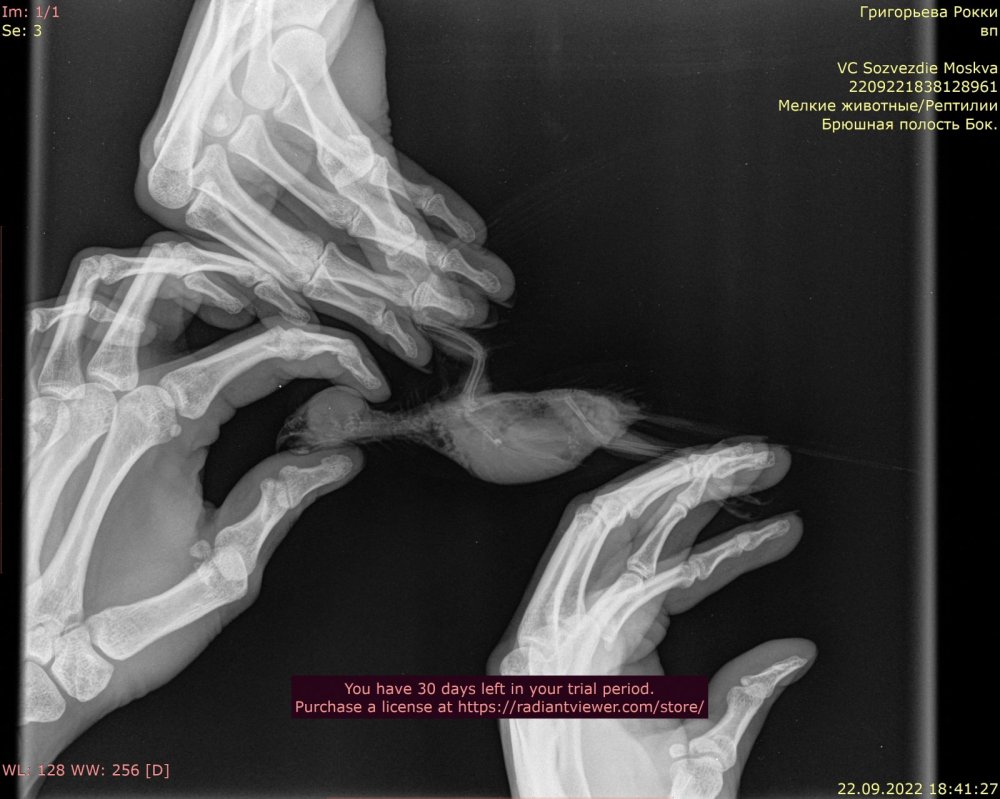

6. Здравствуйте, имеем волнистого попугая с новообразованием семенников. Рентген и заключение врача прикладываю. Читала про такую схему: преднизолон/мелоксикам/ригевидон. Для нас актуально? @Zosia